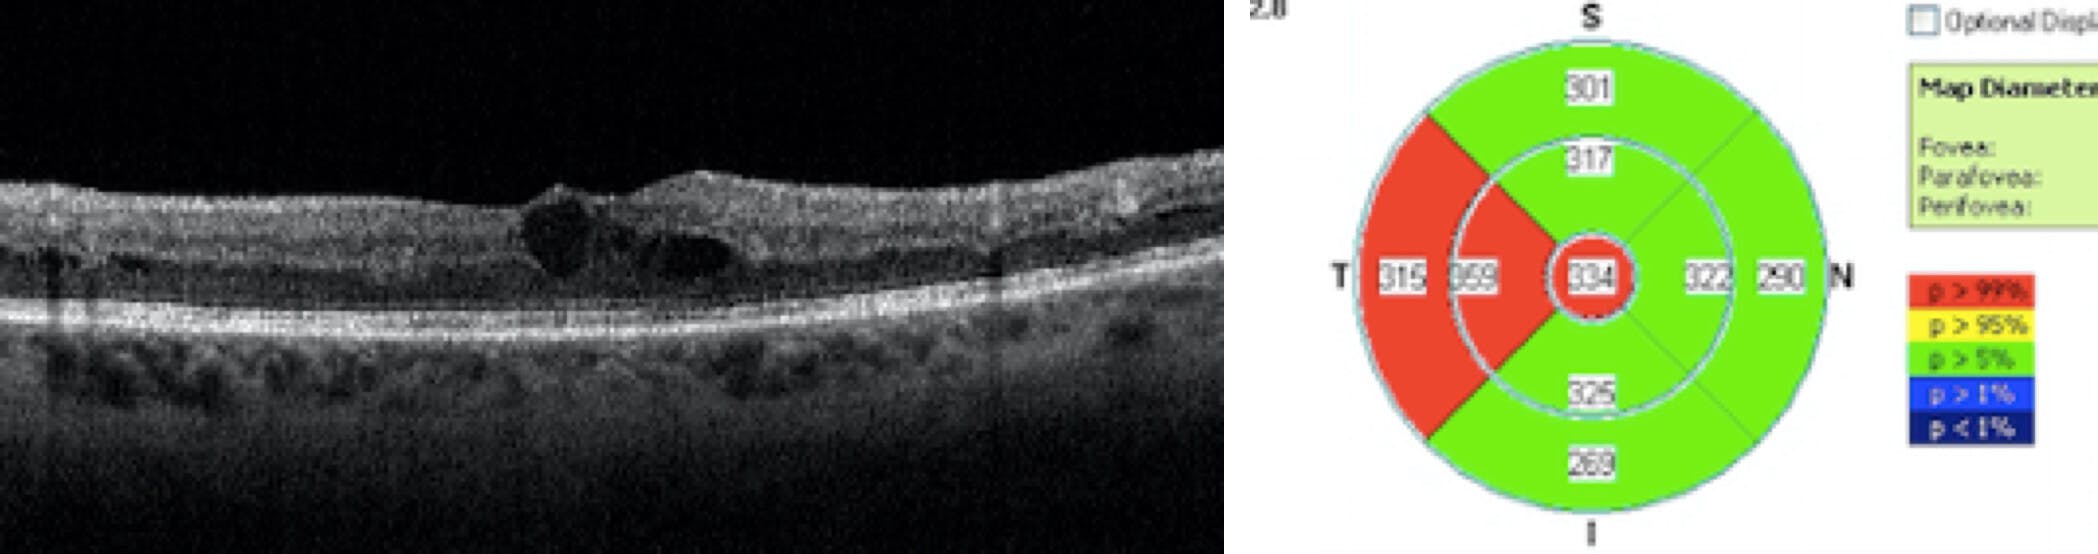

SD-OCT was performed and revealed central subfield thickening OD (Figure 2).

OCT is indicated to assess for the presence of diabetic macular edema (DME), which is more likely to occur as the level of DR worsens. The presence of lipid exudate within the macula bolsters the possibility of coexiting DME. Fluorescein angiography is another useful tool in the evaluation of DME, but mostly likely used as ultrawide-field fluorescein angiography (UWFA) to assess the presence of capillary dropout/nonperfusion (ischemia), intraretinal microvascular abnormalities, or coexiting neovascularization. These cases need treatment and further evaluation by a retina specialist. More recent studies demonstrate that a global DR Severity Score based on full-field flicker electroretinography (ffERG) and pupillary response to the ERG stimulus predicts which patients with DR are most likely to require retinal intervention over the following 3 years,1 with better sensitivity for progression than both standard 7-field DRSS photography and OCT angiography vessel density (RetEval, LKC Technologies), but this test was not available at this patient encounter and would not have altered the decision to refer based on clinically evident DR severity.